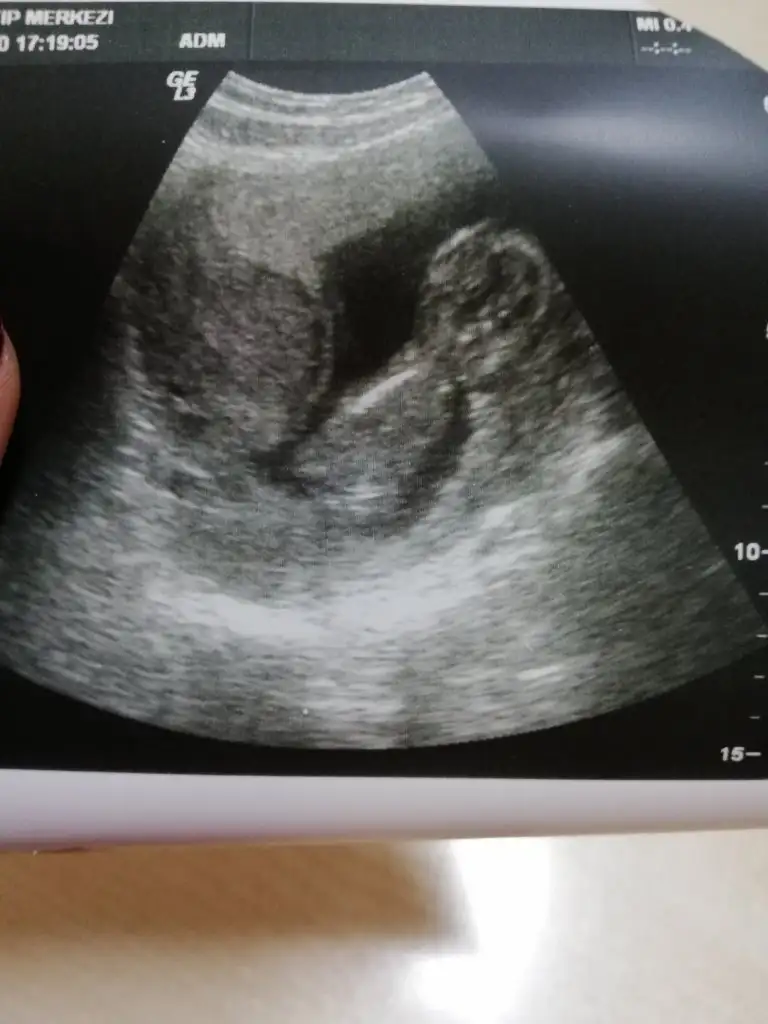

Yanlış yere etiketlemisim Bu iste Mely15Banada tahminde buluna bilir misiniz acaba kizlar

ErkekkkBana da tahminde bulunabilir misiniz Ikra meyra